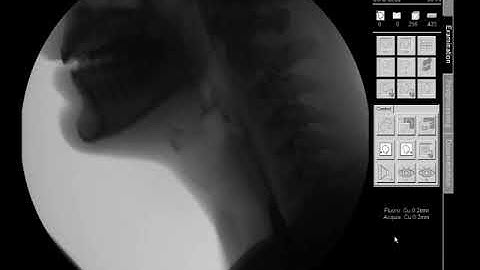

Swallow Study - Solid Texture/Cracker - Modified Barium Swallow Study (MBSS) Lateral View HD